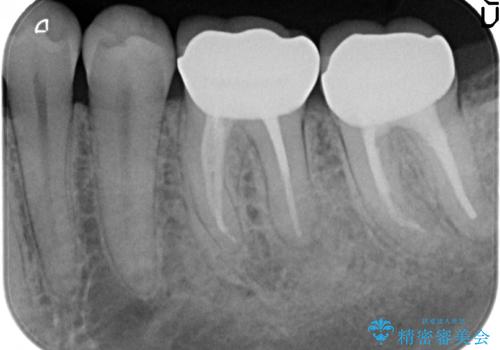

- 左下の奥歯でものを咬むと痛むので診て欲しいといらっしゃった方の症例です。

左下6、7番目の歯に根尖病変を認めたため、再根管治療後、オールセラミッククラウンによる補綴を行いました。